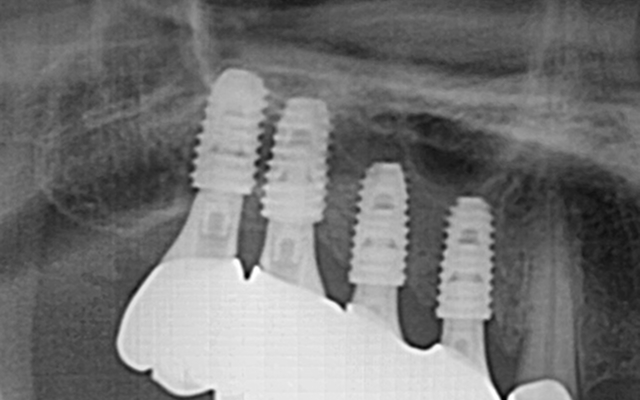

고난도 뼈이식 케이스

- 정밀 영상 진단으로 결손 부위를 파악하여 안전하게 골이식

- 미세 수술 장비를 활용해 식립 안정성 및 성공률 향상